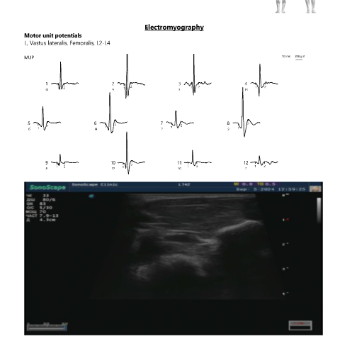

Fully-Synchronized EMG and Ultrasound in One Software

The Neuro-MEP.NET software enables a real-time visualization of nerves and muscles synchronously with EMG recording.

- visualization of motor units

- estimation of motor unit area

The software also enables the user to generate the report summarizing both EMG data and images obtained by an ultrasound scanner. This data is stored in the archive and can be reviewed if needed.